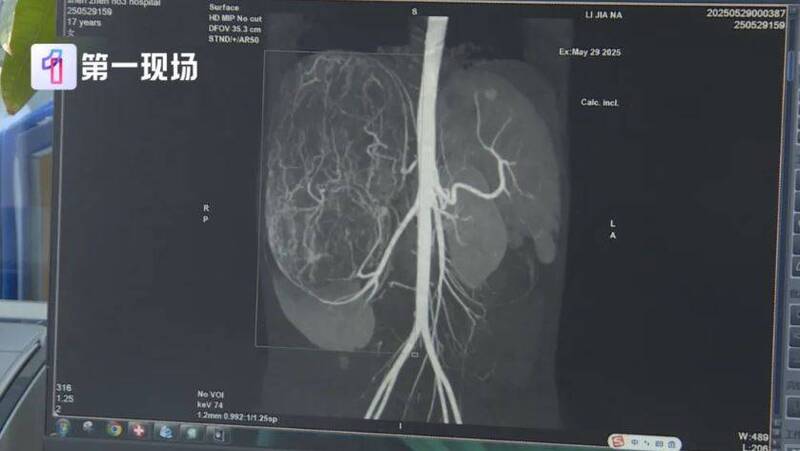

婷婷到医院检查发现,她的右肾有恶性肿瘤伴随肝转移可能。

广东省深圳市第三人民医院肾移植二科主任胡红星表示,婷婷的情况不能等,必须及时将肿瘤切除。只是肿瘤体积过大,几乎占据整个腹腔,周边器官也被严重挤压,留给医师手术空间实在有限。

所幸最终成功将肿瘤切除,胡红星说:“我们测量了大小有27公分,重量有2.435公斤,非常非常的大,切得非常完整。”